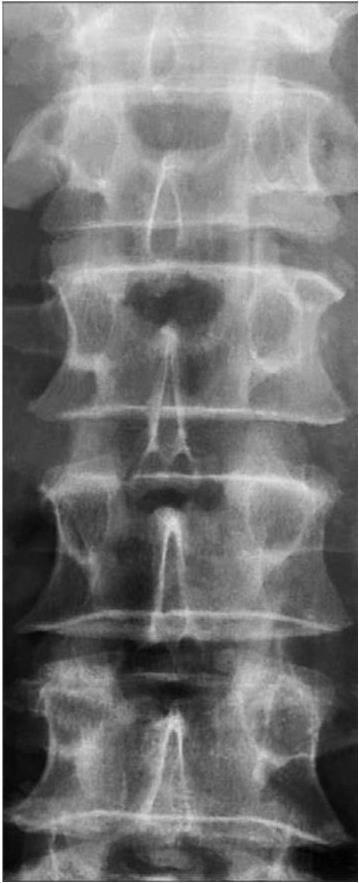

Рис. 5. Рентгенограмма позвоночника больной с остеопорозом. Прямая проекция

Тела позвонков по своей плотности приближены к межпозвоночным дискам. Резкая очерченность всех элементов костных структур

Рентгенологически ОП выявляют уже тогда, когда утрачено 25–45 % нормального объема костного вещества. Наличие ОП в позвоночнике не вызывает сомнения в тех случаях, когда тела позвонков по своей плотности приближены к межпозвоночным дискам. При ОП рентгенологически находят резкую очерченность всех элементов костной структуры и непрерывность замыкающих пластинок, их извилистость. При выраженном ОП появляются так называемые рыбьи позвонки, позвонки трески. Это происходит вследствие вдавления межпозвоночными дисками верхней и нижней замыкающих пластинок поверхностей позвонков. Межпозвоночные диски увеличены в размерах и приобретают форму двояковыпуклых линз. Тела позвонков выглядят «стеклянными». Высота тел позвонков уменьшена преимущественно в переднем отделе, но иногда и на всем протяжении. Позвонок виден в виде пластинки небольшой толщины. Чаще бессимптомные переломы укорачивают переднюю половину тела позвонка, обусловливая его клиновидную деформацию. Вертикальные трабекулы тел позвонков сохраняются намного дольше горизонтальных, вследствие чего на рентгенограммах определяют вертикальную исчерченность тел позвонков.

С возрастом происходит уменьшение высоты тел позвонков как по передней поверхности, так и посредине. Снижение высоты посредине выражено более значительно. Отмечена тенденция к увеличению переднезаднего размера тел позвонков (их длины). Уменьшен индекс — отношение высоты посредине к длине. Если в 25 лет он равен 85, то в 60–70 лет — 78 (Рохлин Г. Д. [и др.], 1986). Рентгенограмма с выраженными старческими изменениями позвоночника представлена на рис. 5.